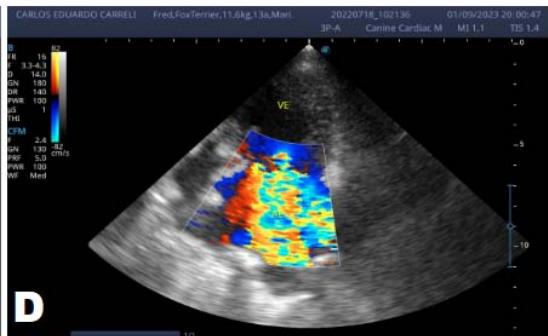

One year later, the animal returned for a new evaluation, repeating the ECHO (Figure 2), which showed the progression of the increase in the left atrium. The electrocardiogram (ECG) (Figure 3) shows baseline sinus arrhythmia with the presence of a premature ventricular complex (Figure 4). Owners report drowsiness, hyporexia, and syncope. However, they did not present tiredness or cough. Blood pressure was 80 mmHg.

Figure 2: Echocardiogram (2022): observed increase in the left atrium and ventricle; thickened/degenerated mitral valve (A); observed in a Doppler study, turbulent systolic flow within the left atrium, characterizing significant mitral valve insufficiency (B); systolic turbulent flow within the right atrium, representing mild tricuspid valve insufficiency (C); hemodynamic assessment - maximum velocity gradient mitral regurgitation: $3.51\mathrm{m / s} / 49.22\mathrm{mmHg}$; observed left ventricular diastolic dimension above normal limits with normal systolic function parameters, characterizing systolic dysfunction; preserved diastolic function

In 2022, the animal returned for annual exams one year after the diagnosis. The ECHO showed an increase in the left atrium and ventricle, thickened/degenerated mitral valve (Figure 2), preserved diastolic function, and low probability of pulmonary hypertension; the ECG detected an increase in the duration of the P wave and the QRS complex (Figure 3), suggestive of atrial and left ventricular overload, baseline sinus arrhythmia with the presence of a premature ventricular complex.